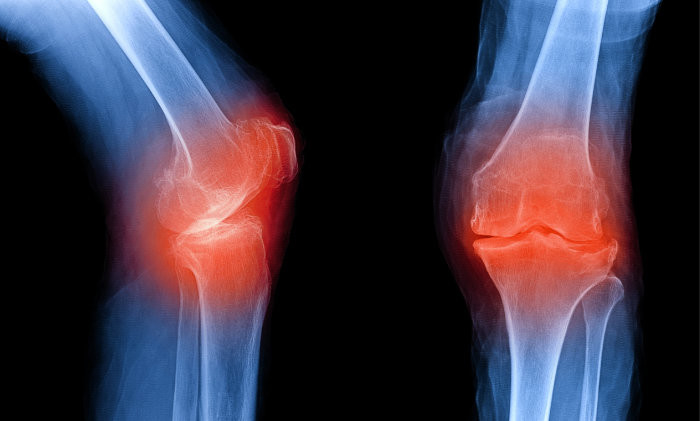

사람들이 나이가 들어감에 따라 자연적으로 관절이 안 좋아지는데요. 우리나라 성인의 만성질환 1위가 관절염이라고 하니 관절염으로 인한 통증으로 많이 불편해 하는 현실입니다. 관절염 통증은 많은 이유가 있겠지만 관절 사이에서 완충 작용을 하는 연골이 닳아서 충돌하면서 발생하는 경우가 많습니다. 이 연골의 주 성분이 콘드로이친 이라는 성분인데요.이 성분이 떨어지면 각종 관절염, 근육통 등 증상이 발생하게 됩니다. 콘드로이친은 우리 몸에서 스스로 생성되지 않는 성분으로 꼭 섭취를 통해서만 보충이 가능하다고 하네요.

콘드로이친의 가장 큰 효능은 바로 연골 감소 예방입니다. 콘드로이친은 연골에 영양분을 공급하는 역할을 합니다. 연골에 충분한 영양분들 공급하여 연골의 탄력과 힘을 보충하여 연골이 마모되는 것을 예방해 줍니다. 한 실험울 통해서 콘드로이친을 일정하게 섭취한 사람과 아닌 사람의 연골 마모 속도가 2배 이상 차이가 난다는 결과가 있습니다.

관절 속 충격완화 및 충격을 방지하는 역할을 하는 콘드로이친 성분으로 하여금 연골 형태 및 탄력을 유지시킴으로 통증은 완화시키고 염증은 억제하는데 도움이 됩니다. 연구 결과 통증 완화 감소 정도가 소염진통제 만큼 뛰어난 것으로 알려져 있습니다.